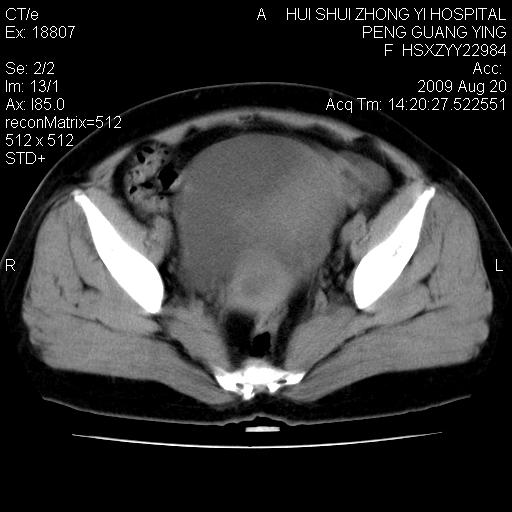

标题: CT21707:女,42岁,因发现下腹部包块2月。 [打印本页]

标题: CT21707:女,42岁,因发现下腹部包块2月。

病灶来源——子宫?附件?

从平扫角度看本人还是倾向于子宫肌瘤诊断,宫腔少量积液。

目前的影像表现显示肿块位于腹腔及盆腔,但具体定位,分清来源较困难,是否来源于卵巢、子宫无法定论,子宫直肠及子宫膀胱周围脂肪间隙尚较清晰,如果患者有过腹腔好或者盆腔手术史,也可以形成不典型的血中,最好手术后定为定性,我期待结果。

软组织密度,与子宫一致。双侧卵巢形态、密度好,不支持来源于卵巢。